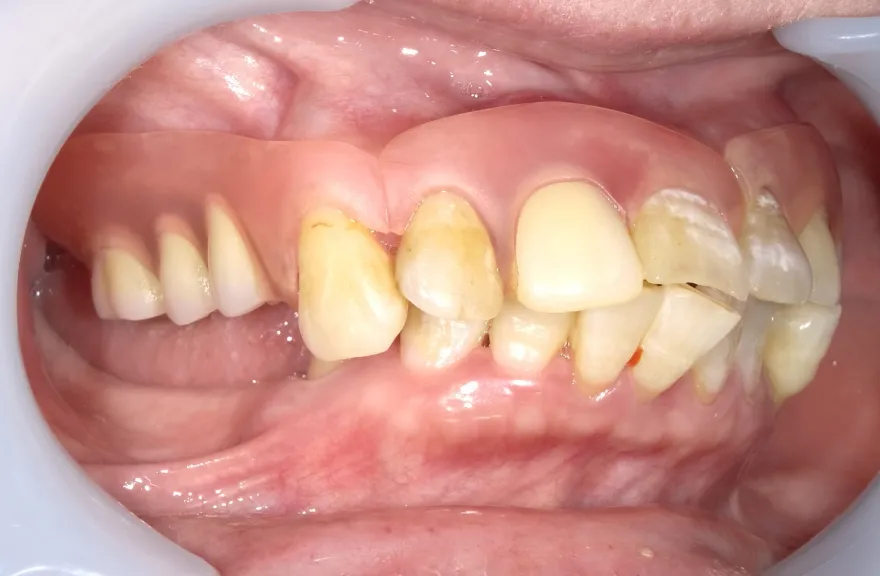

【治療例 2】金属を白くしたい63歳

- 相談内容

-

右上の奥歯が取れたということで来院されました。

各所の金属は昔に治療されたもので、外してみるとどれも虫歯になっていました。

一つずつ虫歯治療を行い、インプラント治療、矯正治療を並行して行いました。 - 治療費用・方針

写真の通りに治療を終了いたしました。

各所虫歯に侵食されていましたが、歯を残すことができたのでインプラントの数をおさえることができました。

下の前歯が先天的に1本欠損しており、そのため噛み合わせを構築することが難しいケースでした。矯正治療を併用することで前歯と奥歯をバランスよく噛ませることに成功しました。